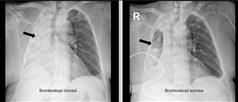

Prof. Dr. Göksel Altınışık Ergur shared the following information: “Foreign body aspiration into the airways usually occurs as a result of sudden and unexpected incidents. Normally, the epiglottis, located between the esophagus and the windpipe, prevents food from entering the airways by mistake. However, this protective mechanism may fail during situations such as laughing, talking, or feeding patients in a lying position. When foreign objects like nuts, chickpeas, liquids, needles, or dental prostheses enter the airways, the body reacts strongly through the cough reflex. Depending on the size of the object and where it becomes lodged, symptoms such as shortness of breath, cyanosis, and even death can occur. If the object cannot be expelled through the Heimlich maneuver or coughing in the initial stage, bronchoscopy is required. This procedure is typically performed under general anesthesia using a rigid bronchoscope, a metal tube. Failure to remove the object can lead to lung collapse (atelectasis) due to the cessation of air flow and result in persistent infections, potentially causing permanent lung damage. Foreign body aspiration is not limited to children; it can occur in adults as well. Early diagnosis and proper intervention can be life-saving. Our patient, who aspirated a corn kernel, was a 78-year-old retired female teacher who had been bedridden at home due to a stroke resulting from a cerebral artery blockage 11 years ago. Although she was conscious, she was entirely dependent on bed care and unable to perform daily activities. She was also undergoing treatment for heart failure and epilepsy. In recent months, she had frequent hospitalizations due to lung infections, and a bronchoscopy performed at another center a month ago had revealed no problems. Since bedridden patients are at high risk of frequent infections, hospital admission and bronchoscopy were appropriate approaches. The patient was referred to us after her latest admission to another hospital, where a CT scan revealed complete closure of the right lung.”

Stating that emergency bronchoscopy was planned and promptly performed after it was confirmed from previous tests that the airway to the right lung was completely blocked, Prof. Dr. Altınışık Ergur noted that the patient’s medical history lacked signs typically associated with foreign body aspiration—such as coughing, cyanosis, or sudden shortness of breath—thus making it necessary to determine the underlying issue. She continued: “While examining the airways with a flexible bronchoscope, we observed very dense and dark secretions. It was clear that a thorough cleaning was required to proceed. Using an aspirator (a device that removes internal fluids), sterile fluid was administered and suctioned to clear the airways. Then, a yellow object was detected in the airway leading to the right lung. It was clearly a foreign body, and its resemblance to a corn kernel was evident. While this could have been treated with rigid bronchoscopy under general anesthesia, due to the patient’s poor overall condition—especially considering her comorbidities and infection—the risks of general anesthesia were high. Therefore, we opted to attempt removal at that moment. By using the suction power of the aspirator, it was possible to extract the object. The tip of the bronchoscope was placed against the body of the yellow object, and through suction, the two were tightly adhered to each other. By carefully maintaining the suction power, the foreign object and bronchoscope were successfully removed from the airways together. After the procedure, when the patient’s relative was asked again about any relevant medical history involving corn, it was revealed that the patient had eaten pizza topped with corn five months earlier. Since there had been no immediate symptoms, the possibility of aspiration had not been considered. This case, showing that such events can occur without notice in frail patients eating solid foods, highlights the importance of evaluating such patients with the thoroughness of a detective.”